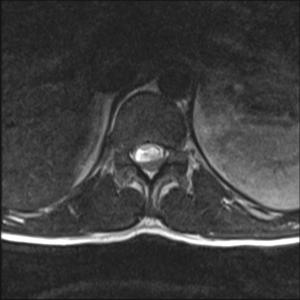

Can you diagnose this patient with low back pain, right lower extremity paraesthesias, and incontinence?